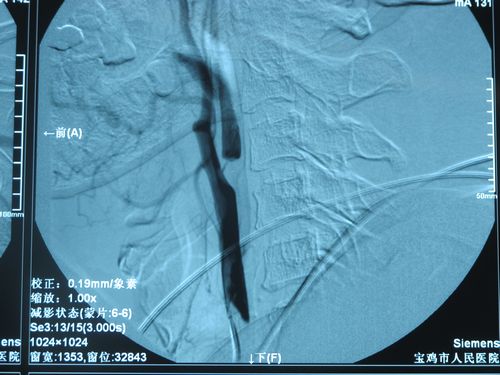

2012年6月27日,北京安贞医院脑卒中中心主任、中美脑中风协作组中方组长张勤奕教授在安贞医院为两例患者实施了颈动脉内膜剥脱术,手术圆满成功。

患者赵某某,男,60岁,主因“间断左侧肢体麻木3年,突发右侧肢体无力20天”入院。患者3年来间断出现左侧肢体麻木,每次发作持续数分钟可缓解,曾于当地医院检查,给予阿司匹林口服,间断中成药物静点。20天前晚上突发左侧肢体活动不能,右侧面部歪斜,伴抽搐,于当地医院急诊住院,查头CT示右侧脑室旁间隙脑梗塞,经股动脉穿刺行全脑血管造影,结果示右颈内动脉起始段全闭塞,立即给予静脉溶栓,后患者肌力恢复至4级左右,后未再复发。为求进一步诊治收安贞医院脑卒中病房。

患者李某某,女,61岁,主因“间断胸闷伴心悸2年”于2012你那6月5日入院。入院完善各项辅助检查,给予抗血小板、扩冠、抗凝及改善循环治疗,行冠脉造影示三支病变,遂转入心脏外科行不停跳冠脉搭桥术,手术顺利,术后恢复可;患者住院期间行全脑血管造影术示左颈总动脉重度狭窄,左椎动脉闭塞。患者具备CEA手术指征,冠脉搭桥术后已10日,生命体征平稳。2012年6月27日,张勤奕教授为其施行了颈动脉内膜剥脱术,手术圆满成功,患者恢复良好。